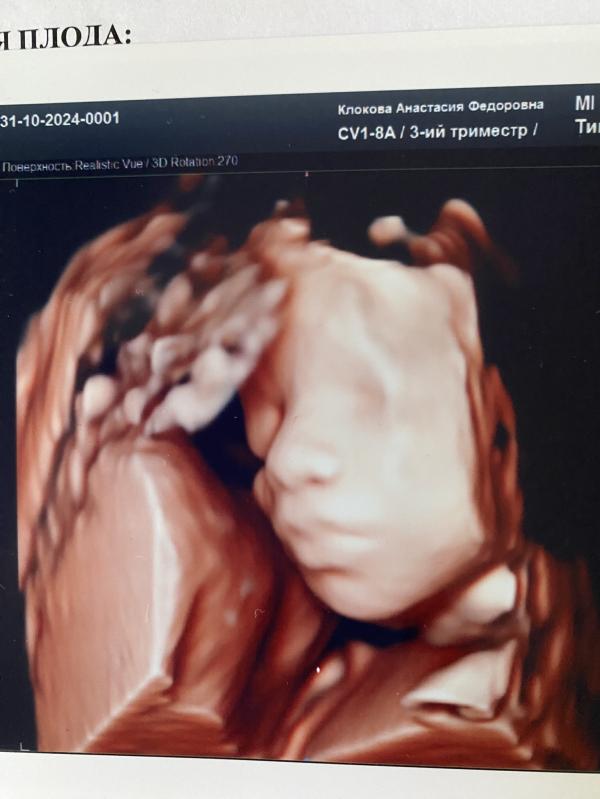

Да , сегодня была на узи , сказали нет признаков инфицирования внутриутробного , воды в норме , кровоток в норме , все хорошо по узи! Спасибо за заботу ❤️

Как у вас дела? На УЗИ что сказали, всё хорошо? После ветрянки. 🙏

Малыш(ка) красотка (или красавец) 😍🫶